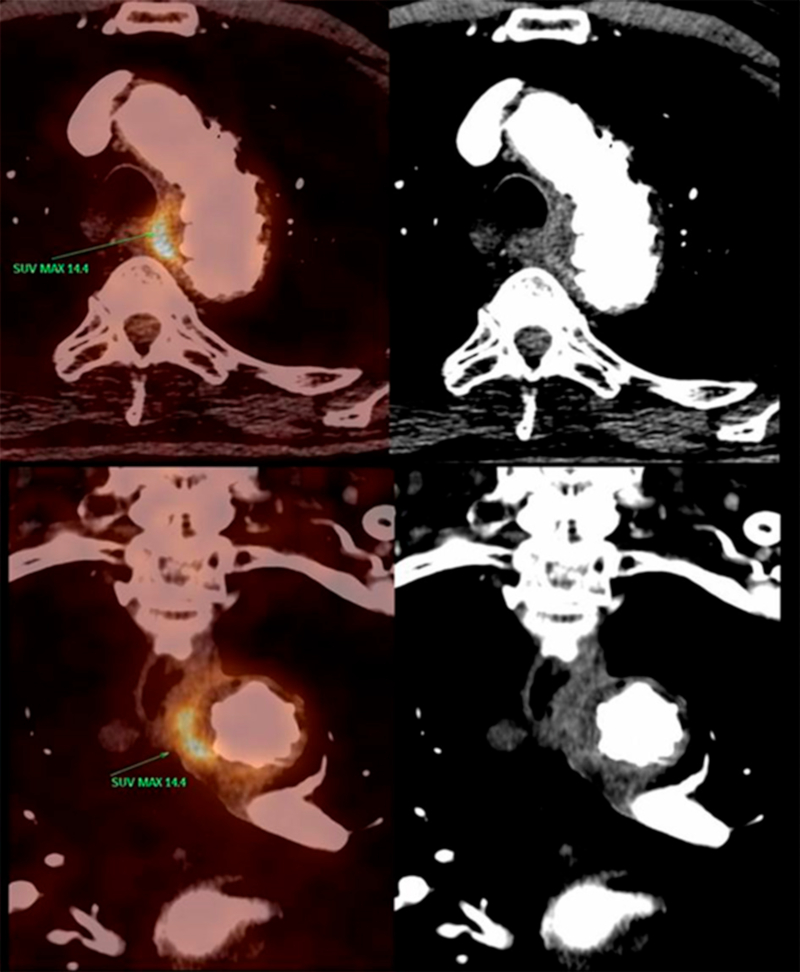

Se decidió realizar una PET/TC 18 FDG (Figura 1) y se evidenció en esta un aumento del espesor de la pared del cayado aórtico, con realce del contraste endovenoso y captación del radiotrazador con un índice de captación estandarizado máximo (SUV máx) de 14,4 a predominio del sector medial y en menor medida del inferior. La úlcera se encontraba correctamente excluida, sin evidencias de endofugas ni expansión. La endoprótesis aórtica no presentaba signos de captación patológica.